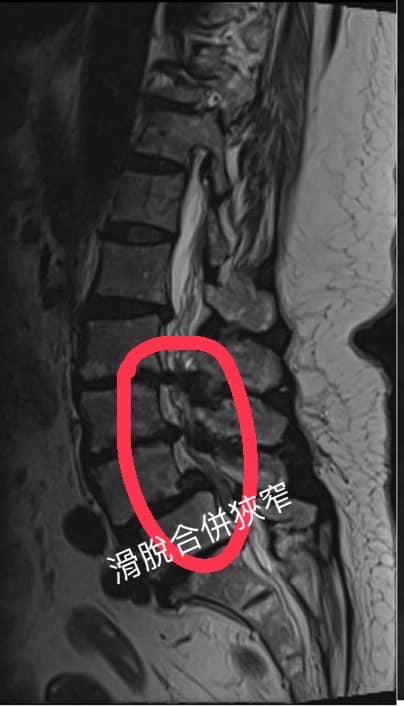

Cervical Spine Treatment Cases 腰椎治療案例 ⭕️腳麻腳冷腰臀疼痛,當心脊椎管狹窄症 🛑五大症狀自我檢測 ❗️腿麻走不動之脊椎狹窄一... 2022.04.06 #腰椎滑脫合併椎管狹窄醫案 #原本痛到無法走路跟坐車 #脊椎整合中醫微創逆轉勝 #治療... 2022.04.02 ➡️腰椎開過三次刀心酸血淚史醫案 🔄什麼時候要考慮打釘子跟置放椎間盤 🟢什麼是下背手... 2022.03.25 👍感謝台北市士林區社子區葉大姐熱情見證 🥲嚴重椎管狹窄醫案原本大痛到寸步難行 😄十... 2022.03.24 #腰椎滑脫合併椎管嚴重狹窄醫案 #感謝新北市汐止區廖伯伯熱情見證 #腰腿疼痛到寸步難... 2022.03.09 #感謝饒河夜市知名餐廳連老闆熱情見證 #腰椎疼痛超過三年曾經大痛到無法走路 #腰椎間... 2022.03.03 #打過四次PRP跟三次類固醇的長期腰痛 #多年來無法正常前彎超過90度 #髂腰韌帶合... 2022.02.24 #腰酸屁股痛長達六年的年輕修車師傅 #大痛到去醫學中心打止痛消炎針數次 #醫學中心復... 2022.02.22 #腰椎滑脫合併椎管嚴重狹窄醫案 #感謝台中市北屯區呂阿姨熱情見證 #原本腰腿疼痛到快... 2022.01.04 #八十老翁腰椎手術兩次仍然不理想 #治療前無法在忠孝東路走超過一分鐘 #忠孝復興交會... 2021.12.29 感謝台看過四家復健科、骨科、醫學中心、整骨,依然效果不如預期,右腳依然麻痛到不行... 2022.02.18 #腰椎滑脫合併嚴重椎管狹窄醫案 #兩個醫學中心骨科醫師都建議開刀 #感謝基隆市信義區... 2021.12.22 ⭕️下背手術失敗綜合症候群 🔲腰椎做過一手術切除骨刺 ‼️半年後又開始復發了 ✳️晨起疼... 2022.01.29 🔎腰椎滑脫心酸血淚史 ‼️原本右腳無法走路合併膝蓋痠軟無力 ✅治療六週徹底改善所有症... 2021.12.14 #腰椎間盤巨大突出脫垂 #原本預計下周要開刀了 #最後真的逆轉勝 #來診前已經痛到無法... 2022.01.29 ← 上一頁 4 5 6 7 8 下一頁 →